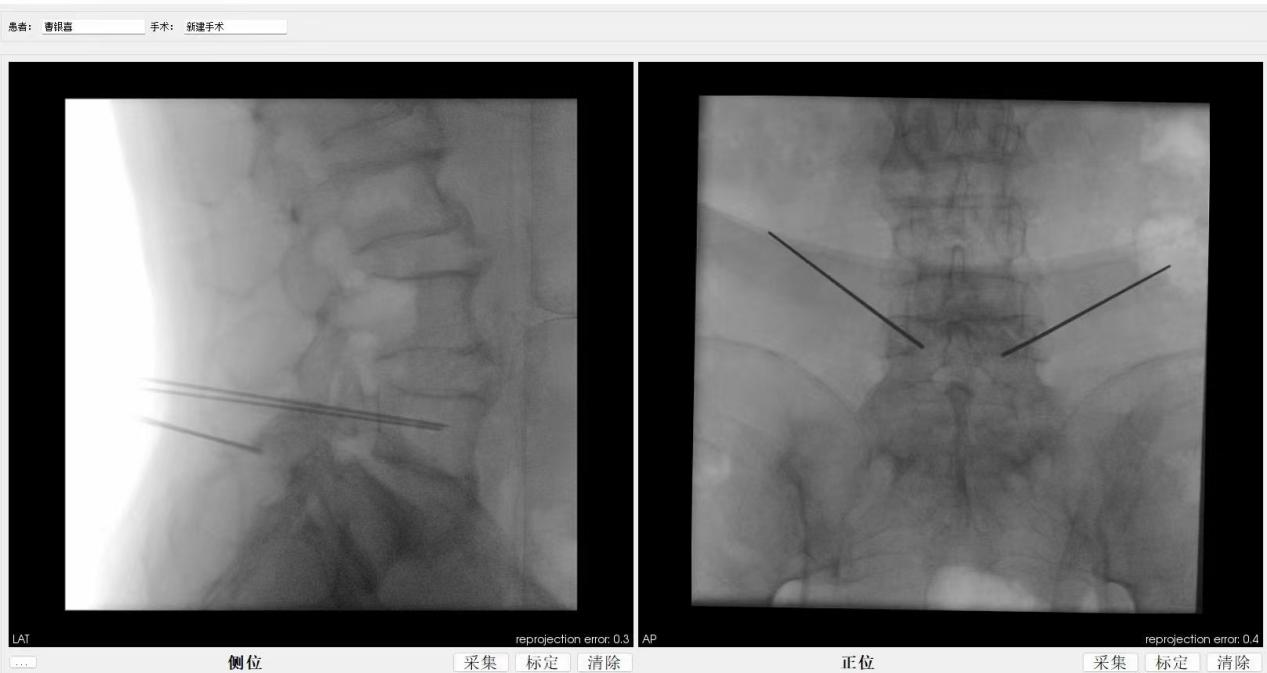

ORTHBOT脊柱机器人术前设计及术中穿刺